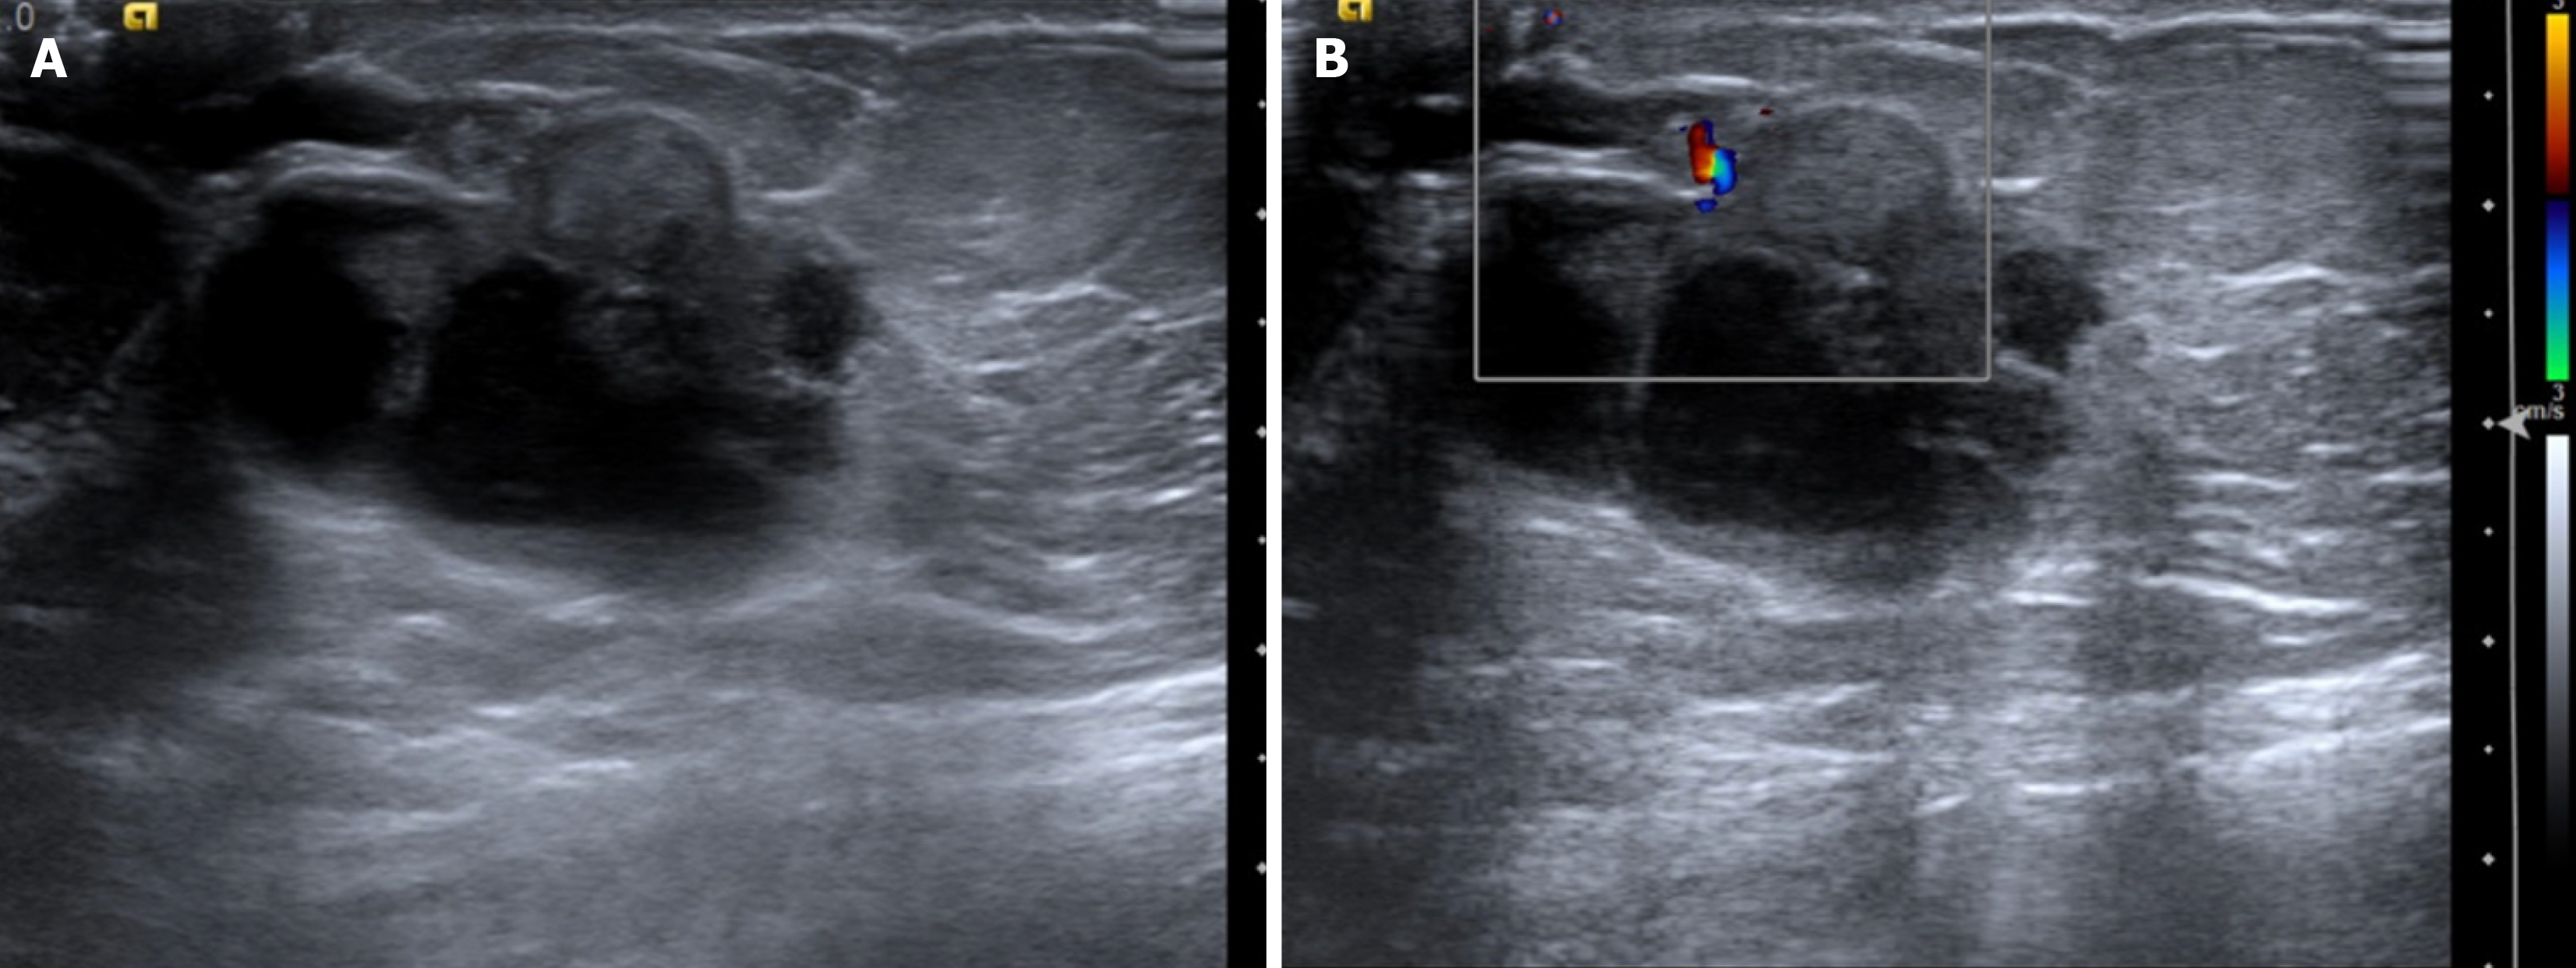

Figure 22  Lymphoma in a 43-year-old male after 3 cycles of chemotherapy.

A: Magnified mediolateral oblique view of the right breast showing a round high-density mass with partially indistinct margins and few punctate calcifications. B: Ultrasound image showing an oval hypoechoic parallel mass with circumscribed margins. C: Histopathology (hematoxylin and eosin, × 40). D: CD20 immunohistochemical staining revealed diffuse large B-cell lymphoma with sheets of atypical lymphoid cells that were positive for CD20.